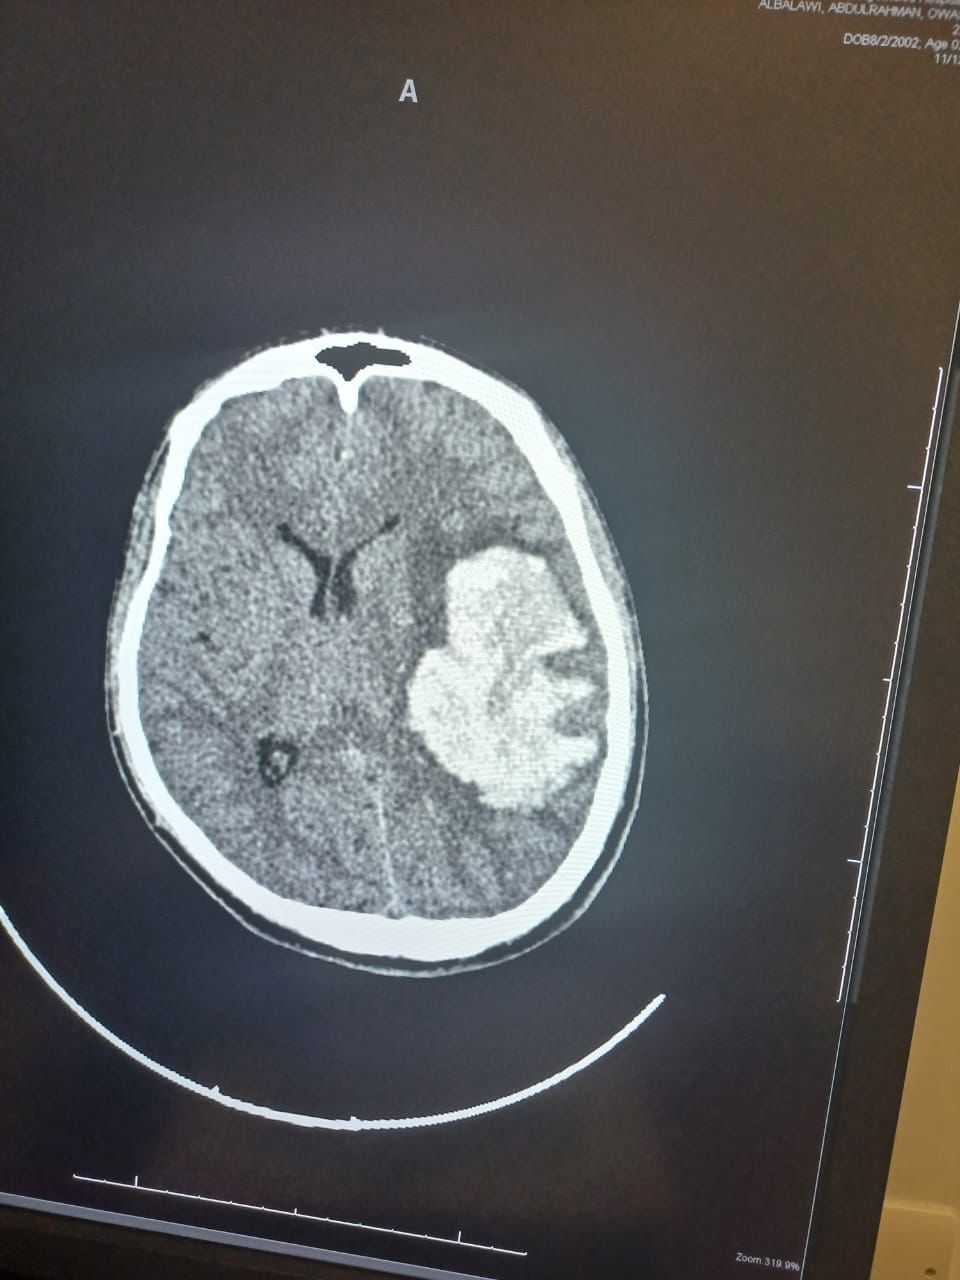

تمكن بفضل من الله فريق طبي من  قسم جراحة المخ والاعصاب  بمستشفى الملك خالد التابع للتجمع الصحي بتبوك من انقاذ حياة شاب بالعشرين من عمره وصل الى قسم الطوارئ وهو في حالة فقدان للوعي وبعد عمل الفحوصات اللازمة وتصوير الاوعية الدموية الدماغية تبين وجود نزيف دماغي حاد في الجهة اليسرى كذلك وجود تشوه خلقي دموي وعائي كبيرا جدا.

وأوضح الفريق الطبي من  قسم جراحة المخ والاعصاب  بالتجمع بانه تم فورا ادخال المريض الى غرفة العمليات واجراء استئصال للأوعية الدموية مجهريا حيث استغرق اجراء العملية أكثر من 5 ساعات تكللت ولله الحمد بالنجاح كما تم تحويل المريض لقسم التنويم بمتابعة وإشراف الفريق الطبي.